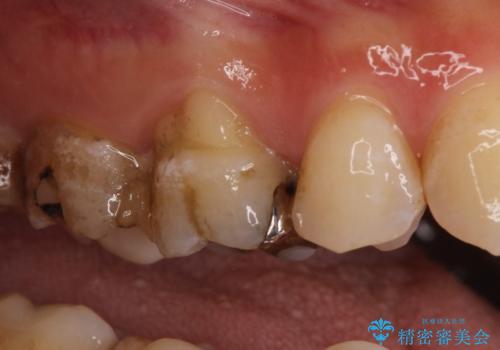

- 奥歯がかけたことを主訴に来院されました。

オールセラミッククラウンにて修復治療を行っております。

歯の破折強度を高めるためにクラウンによる修復を希望され、治療を行っております。